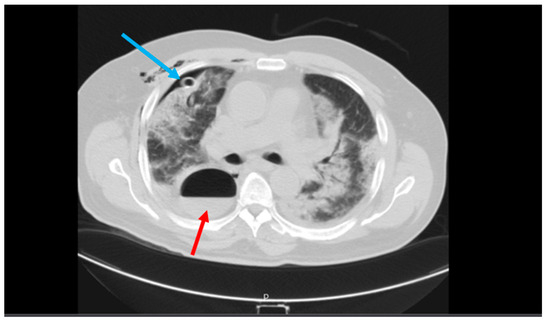

The patient underwent serum therapy and a standard treatment for gastrointestinal bleeding (GIB), including sufficient hydration, IV proton pump inhibitor (PPI) (pantoprazole 40 mg/IV/BID), upper GI endoscopy, and colonoscopy. The endoscopy results were normal, but a grade 4 hemorrhoid was reported. No bleeding hemorrhagic gross lesion was observed. A new lung CT was performed for the patient, which showed a cavity with a thick and irregular wall with an air-fluid level suggesting a pulmonary abscess in the left upper lobe (LUL). Bilateral diffuse GGO lesions with septal thickening, as well as mild bilateral effusion, were also observed (Figure 4). A pulmonary CT angiography was performed to rule out pulmonary thromboembolism (PTE), which showed no evidence of PTE.

Figure 4.

A cavity with a thick and irregular wall with an air-fluid level suggesting pulmonary abscess in the left upper lobe (red arrow). Bilateral diffuse GGO lesions with septal thickening as well as a mild bilateral effusion were also observed (blue arrows).